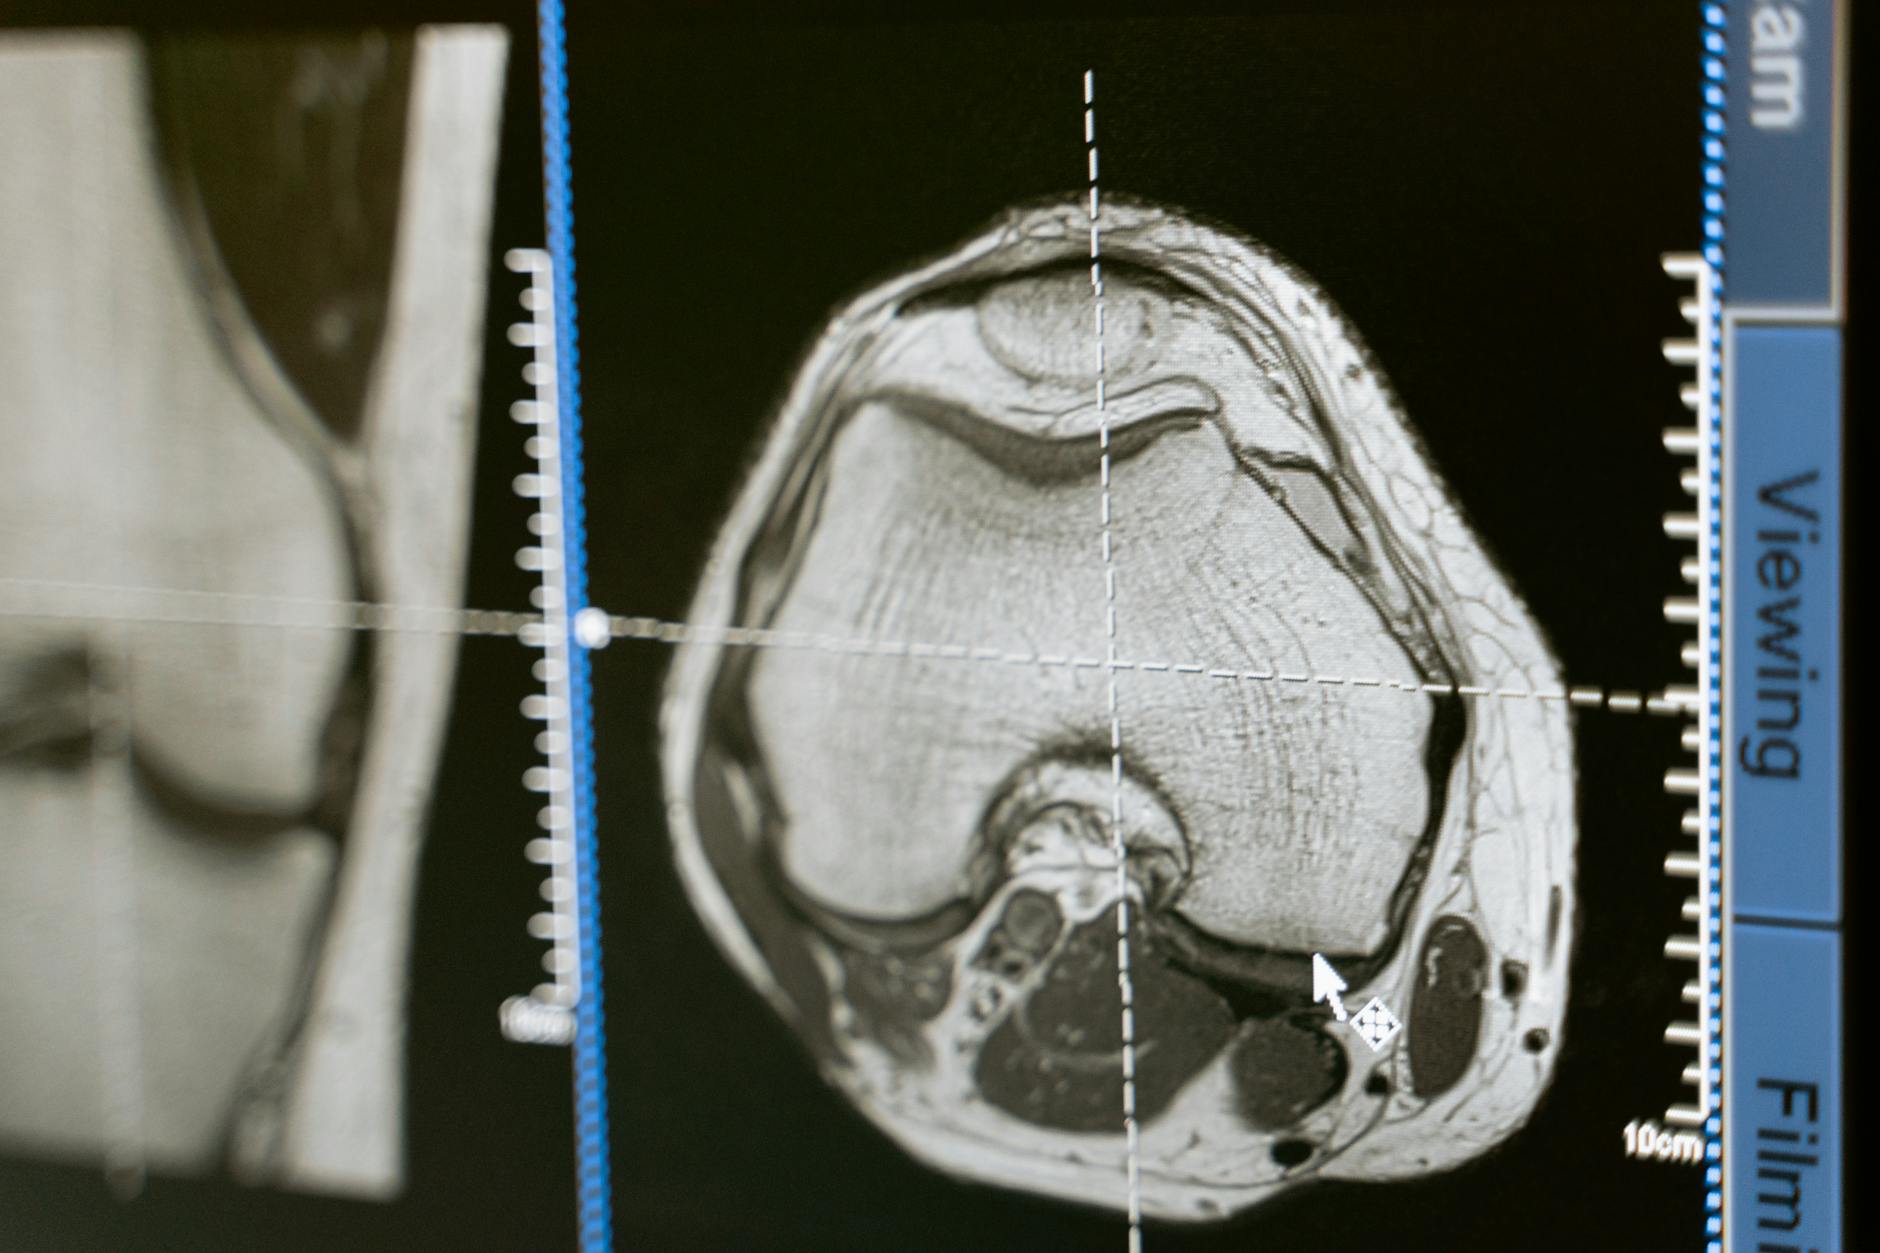

O texto melhora quando mostra que a RM pré-tratamento não serviria apenas para diagnóstico e estadiamento, mas também para antecipar comportamento biológico. Esse é um deslocamento importante: usar características de imagem para orientar intensidade de vigilância e talvez até decisões terapêuticas futuras.

O artigo acerta ao lembrar o peso clínico do carcinoma hepatocelular e da recorrência precoce. Em fígado, risco não depende de uma única variável; depende de tumor, fígado de base, tratamento realizado e contexto do paciente. O score de RM precisa ser lido dentro dessa moldura.